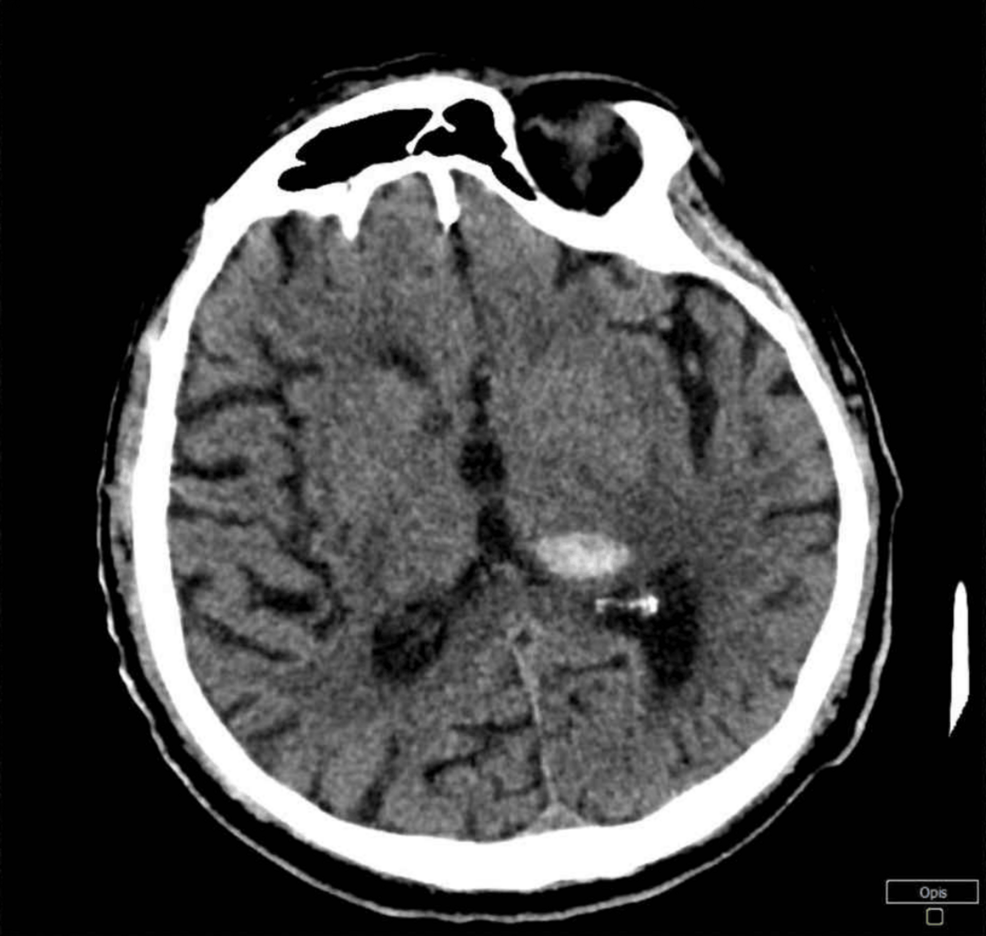

Initial Presentation & Diagnosis:

* Neurological examination revealed right hemiparesis and aphasia.

* CT scan of the head confirmed a left parietal lobe intracerebral hemorrhage (ICH). This classifies the stroke as a cerebral hemorrhage.

* Initial blood glucose was 280 mg/dL.

* Renal function tests showed elevated creatinine and proteinuria.

* Further investigation revealed microalbuminuria, indicative of diabetic nephropathy.